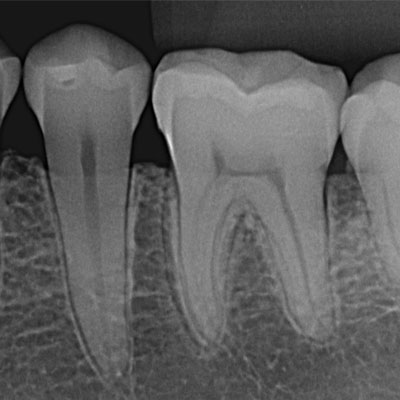

O exame radiográfico periapical proporciona ao dentista a visualização do dente em toda sua extensão, desde a coroa ao ápice, o espaço periodontal e o tecido ósseo.

A radiografia periapical ou RX periapical é um exame utilizado para mostrar radiograficamente a anatomia de um ou mais dentes (desde a coroa ao final da raiz), assim como as estruturas anatômicas vizinhas, ou seja, que estão ao redor dos dentes.

Esta radiografia pode ser usada para estudar qualquer dente (molar, pré-molar, e incisive os caninos) seja na arcada dentária superior ou na inferior para fins de diagnóstico e tratamento.